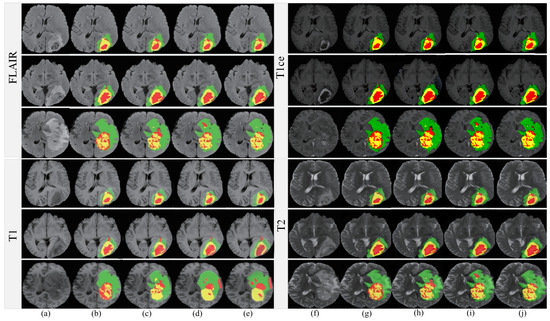

4.6. Qualitative Analysis